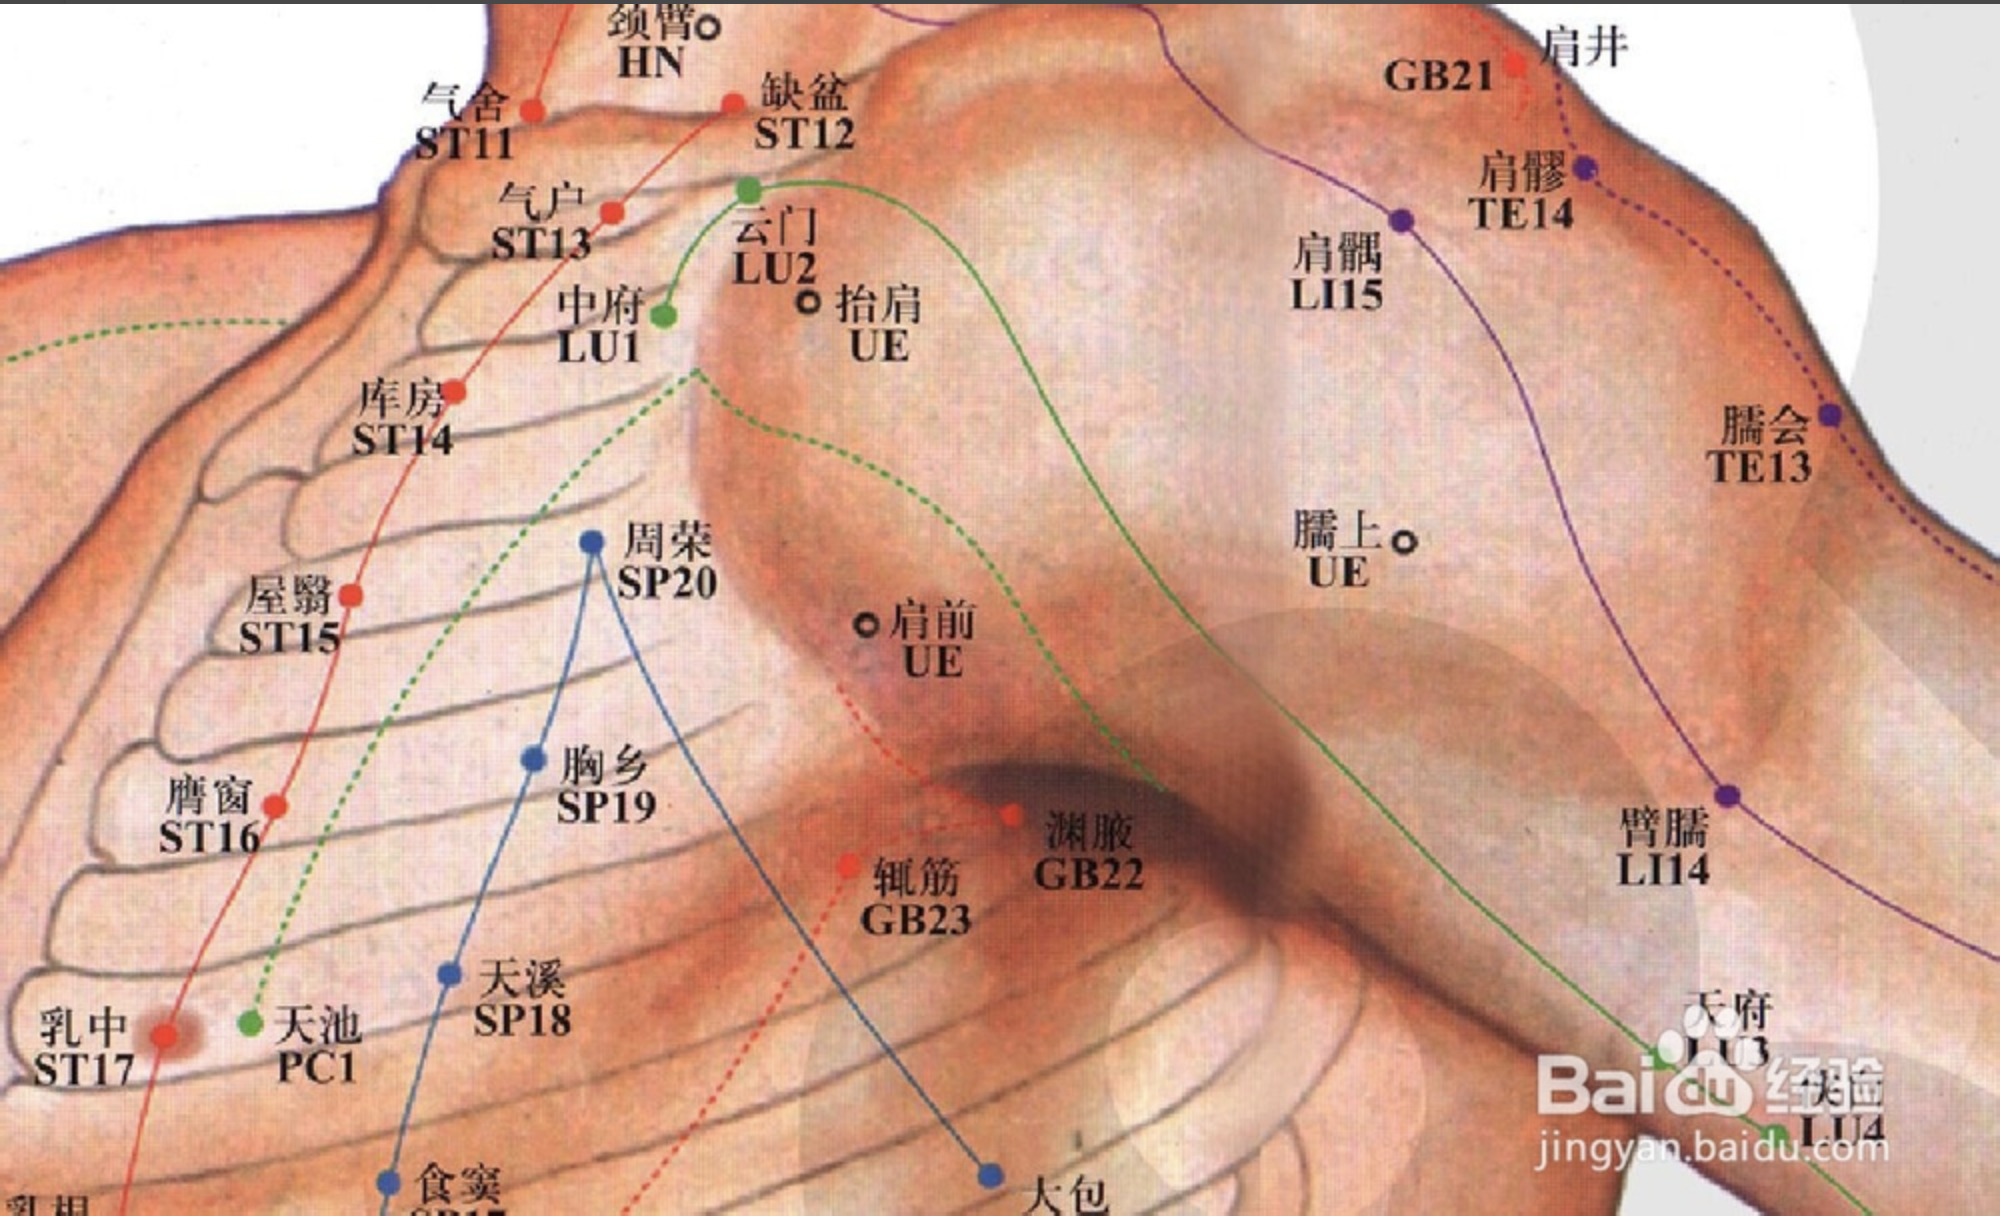

肩井

【定位】 在肩上,前直乳中,当大椎与肩峰端连线的中点上。

【主治】 肩背痹痛,手臂不举,颈项强痛,乳痈,中风,瘰疬,难产,诸虚百损。

【配伍】 配足三里、阳陵泉治脚气酸痛,治疗乳腺炎特效穴。

【刺灸法】 直刺 0.5 ~ 0.8 寸,深部正当肺尖,慎不可深刺;可灸。

【附注】 足少阳、阳维之会。